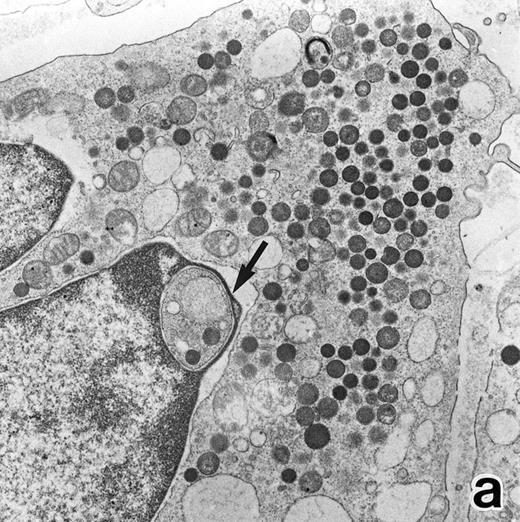

Electron microscopic observation.The leukemic cells of all three patients possessed abundant spherical (type I) primary granules containing electron-dense homogeneous material, with a peripheral halo in some granules and dilated rER (Fig 2a). Although type I primary granules predominated in all patients, small numbers of cytoplasmic granules containing crystalloid structures (type II primary granules) were also present in patient no. 1. Nuclear configurations were irregular, and the chromatin was only slightly condensed along the nuclear membrane. In addition to numerous Auer rods, the cells of patient no. 1 contained large cytoplasmic inclusion bodies also seen under the light microscope. These are the structures surrounded by a unit membrane and filled with parallel tubular material identical to that of Auer rods and belong to the psuedo–Chediak-Higashi (C-H) category of granules20,27 (Fig 2b). The cells of patient no. 3 contained smaller cytoplasmic granules than those of the other patients, and Auer rods were less frequently observed, a finding consistent with the M3 variant. Stellate rER complexes and fibrillar structures in the rER, both of which are thought to be structures specific to APL,28 were detected in this patient.

(a) A bone marrow leukemic cell in patient no. 1 at diagnosis containing abundant abnormally shaped primary granules, including Auer rods and Chediak-Higashi–type inclusions. Dilatation of rER is remarkable. (Original magnification × 10,800.) (b) Higher magnification of a cytoplasmic inclusion body of another cell in patient no. 1 that is membrane-bound and contains bundles of filamentous structures, similar to Auer rods. (Original magnification × 25,800.)